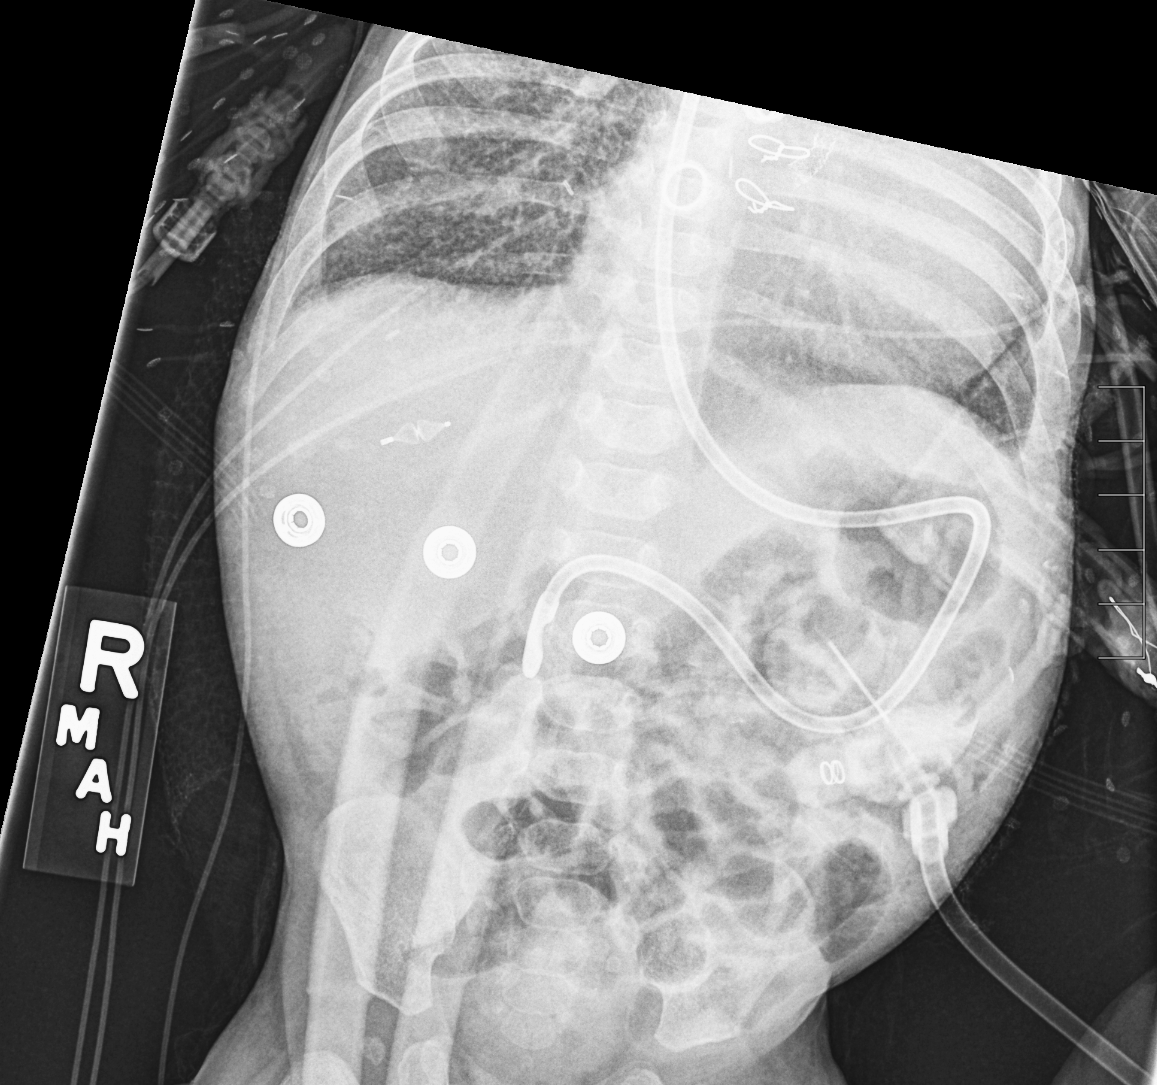

Section 1 Submit Findings CB1550 Findings Skeletal Survey - Technique Check Skull AP/Lat Yes No Cervical and Thoracolumbar spine Yes No Chest X-Ray Yes No Ribs – Left/Right Oblique Yes No Abdominal X-Ray Yes No Pelvis with both hips Yes No Bilateral Humerus, Forearm, Hand Yes No Bilateral Femur, Tibia/fibula, feet Yes No Any additional lateral views of the extremities Yes No The exam is over or under penetrated. Yes No The exam may or may not be limited by overlying structures or soft tissues, body habitus, patient positioning, support devices, or motion. Yes No The area of concern is indicated by the patient, technologist, or care provider. Yes No The area of concern is included on the exam. Yes No Soft Tissues There is soft tissue swelling, indistinctness of fat/muscle planes, gas, or laceration in the area of clinical concern. Yes No There is an effusion, fat pad displacement, or fat fluid level. Yes No There is a radiodense or lucent foreign body. Yes No There are other densities, calcifications, post-surgical changes, or support devices in the soft tissues. Yes No Any support lines/tubes. Yes No Bone There is a break or interruption of the continuity of the cortical or cancellous bone. Yes No There is overriding of the trabeculae with apparent sclerosis. Yes No There is displacement of a fracture fragment. Yes No There is bowing of the bone in addition to the fracture at the apex of the bowed bone concerning for the greenstick. Yes No There is a spiral fracture of the leg concerning for toddler’s fracture. Yes No There is abnormal angulation or bulging of the cortical surface relative to the normal cortex which could be from a buckle or torus fracture. Yes No There is a displaced fragment which may be from avulsion by a tendon, ligament, or joint capsule or from a comminuted or other fracture. Yes No The stress trabeculae or other trabeculae of the cancellous bone are interrupted or otherwise abnormal. Yes No There is subperiosteal or endosteal reaction which could indicate a healing or subacute fracture or other abnormality. Yes No There is hard/soft callus formation. Yes No There is remodeling of the bone. Yes No There is a corner fracture or metaphyseal lesion that could be from nonaccidental trauma. Yes No There are multiple fractures of different ages. Yes No There are vertebral body/spinous process fractures. Yes No There are rib fractures. Location - posterior or lateral. Yes No There is scapular/sternal fracture. Yes No There are fractures of the digits. Yes No There are wormian bones. Yes No There are intrasutural bones. Yes No There is metaphyseal abnormality (lucencies, increased density, erosion) which may be from something other than injury such as stress, metabolic disease (e.g. rickets with loss or distortion of the zone of the provisional calcification), neoplasm (e.g. leukemia), heavy metals, inflammation, or infection. Yes No There are metaphyseal spurs. Yes No There are bony deformities involving multiple bones. Yes No The bones are gracile. Yes No There are non-healing fractures. Yes No There is/are focal or multifocal lytic/lucent, blastic/sclerotic or mixed density lesion(s) or other abnormality. Yes No Overall bone density is increased or decreased with or without thinning or thickening of the cortical or cancellous bone. Yes No Growth plates, ossification centers, apophyses The growth plate(s) is/are abnormal. Yes No There is widening of the physis from a fracture with or without displacement of the epiphysis (Salter-Harris I). Yes No There is a fracture through the physis which then extends into the metaphysis with or without angulation or displacement (S-H II). Yes No There is a fracture through the physis which then extends into the epiphysis and is intra-articular, with or without angulation or displacement (S-H III). Yes No There is a fracture through the metaphysis, physis, and epiphysis which extends into the joint space with or without angulation or displacement (S-H IV). Yes No There is narrowing of the physis from a compression fracture (S-H V). Yes No The apophysis, epicondyle, secondary ossification center, or accessory ossicle is displaced or otherwise abnormal. Yes No The ossification centers are underdeveloped. Yes No Joints and alignment There is an effusion, fat pad displacement, or fat fluid level. Yes No The epiphysis or subchondral bone is fractured, interrupted, flattened, compressed, impacted, displaced, or otherwise abnormal. Yes No There is an intra-articular loose body or chondrocalcinosis. Yes No The joint is widened, narrowed, dislocated, malaligned, or incongruent. Yes No There is pseudoarthrosis. Yes No Other findings There are developmental changes or other anatomic variants or other existing conditions that may or may not be contributing to symptoms which can or should be further evaluated non-emergently or are otherwise incidental. Yes No The remainder of the exam is abnormal for age. Yes No The lungs show focal airspace opacity. Yes No There is pneumothorax. Yes No There is organomegaly. Yes No There is intra-abdominal calcification. Yes No There is displacement of the bowel loops. Yes No There is free intraperitoneal air. Yes No The bowel loops are dilated/obstructed. Yes No There is paraspinal soft tissue abnormality. Yes No